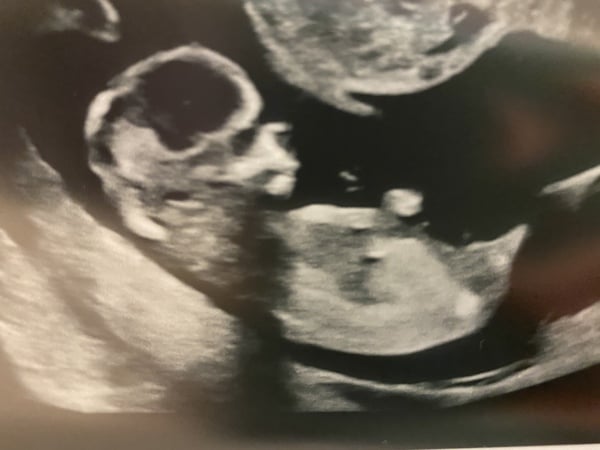

Bellabubble · 25/03/2021 22:59

@MrsTD88 cute scan pic - I had mine on Monday, but he or she had hiccups again and kept hiccuping whenever the lady took a pic so they look a bit stretched out 😂 hopefully my 20week scan will be during a nap time 🤞🏻🤞🏻

@Bellabubble Aww lovely scan pic! Is this your dating scan? How many weeks did you measure as? So cute that that had hiccups.

That's a great scan pic! Will you be finding out the gender?

@Bellabubble that is such a cute scan pic. How far along are you? Apologies I forgot. I can’t wait for my scan now next Tuesday. Usually I had them every two weeks but this time it’s been longer as we will do the harmony test on Tuesday, too and I am anxious to see my baby now. Xxx

@Bellabubble super cute picture!! Glad all is well!

@Bellabubble That's a lovely scan photo.

I remember the sonographer telling us at DD's 12wk scan that she was hiccuping. I had no idea they could even hiccup in there. It's amazing when you see them moving around like that. When is your 20wk scan?

Aw great photo @Bellabubble so cute they had hiccups 😂